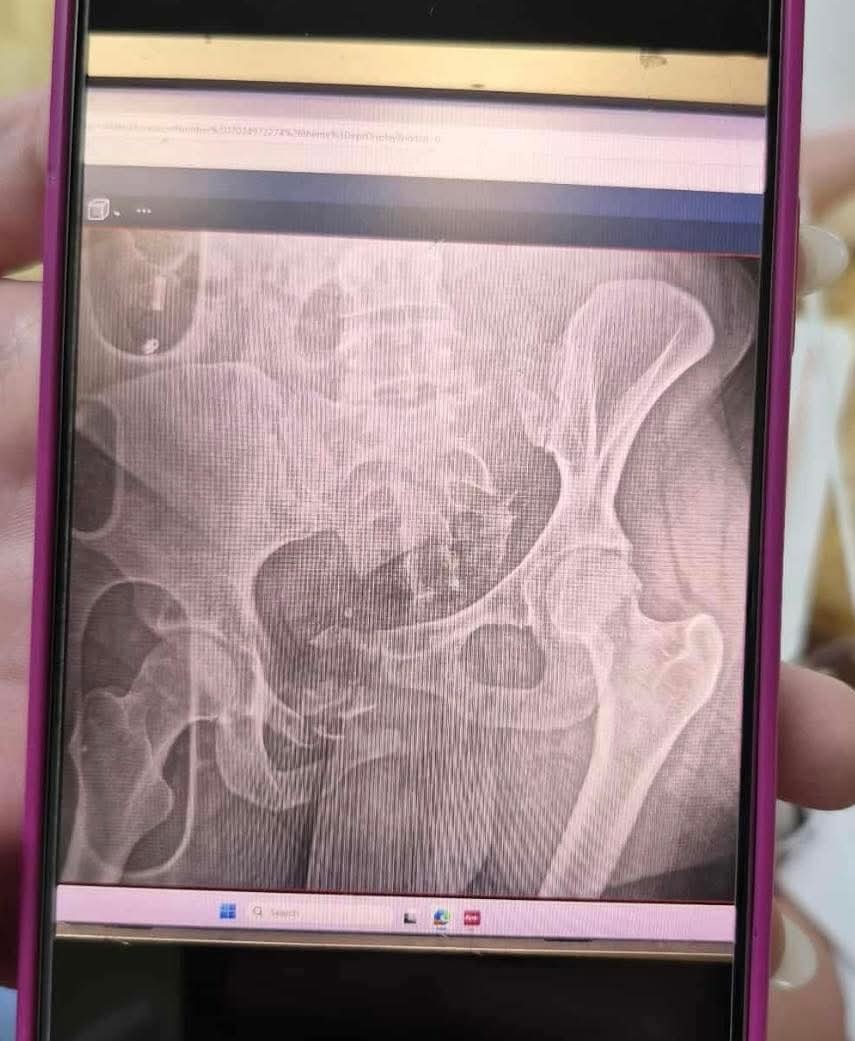

My name is Bri I'm Liannes big sister. Thursday at approximately 2am she was in incident with a vehicle that ended up crushing her pelvis and detaching her hip. She was flown to the hospital where she is now awaiting surgery. She will be here for quite some time and will be sent to rehab to heal and hopefully be able to walk again. She won't be able to work and I'm asking for the community to help if possible and pray if you can't. She's got 4 kids and we're trying to get all the help we can. We appreciate all of you very much!